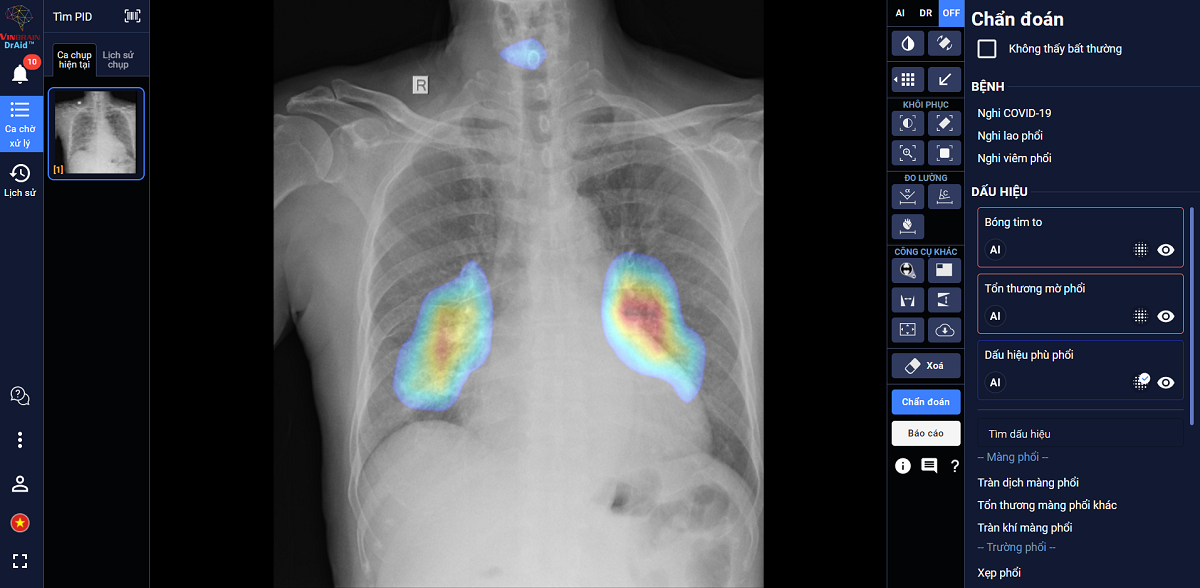

Đây là sản phẩm AI trợ lý bác sĩ với khả năng hỗ trợ chẩn đoán tới tiên lượng điều trị Covid-19 dựa trên ảnh X-quang ngực thẳng. Sản phẩm được ra đời dựa trên kết quả từ đề tài nghiên cứu của Cục Quản lý Khám chữa bệnh - Bộ Y tế và Công ty VinBrain là đồng chủ nghiệm đề tài.

DrAid được đào tạo dựa trên nguồn dữ liệu lớn, gồm 21.421 hình ảnh X-quang ngực của bệnh nhân dương tính với SARS-CoV-2 và 118.018 ảnh X-quang ngực tiêu chuẩn, đạt độ chính xác trên 90%.

DrAid có thể hỗ trợ chẩn đoán tới tiên lượng điều trị Covid-19 dựa trên ảnh X-quang ngực thẳng.